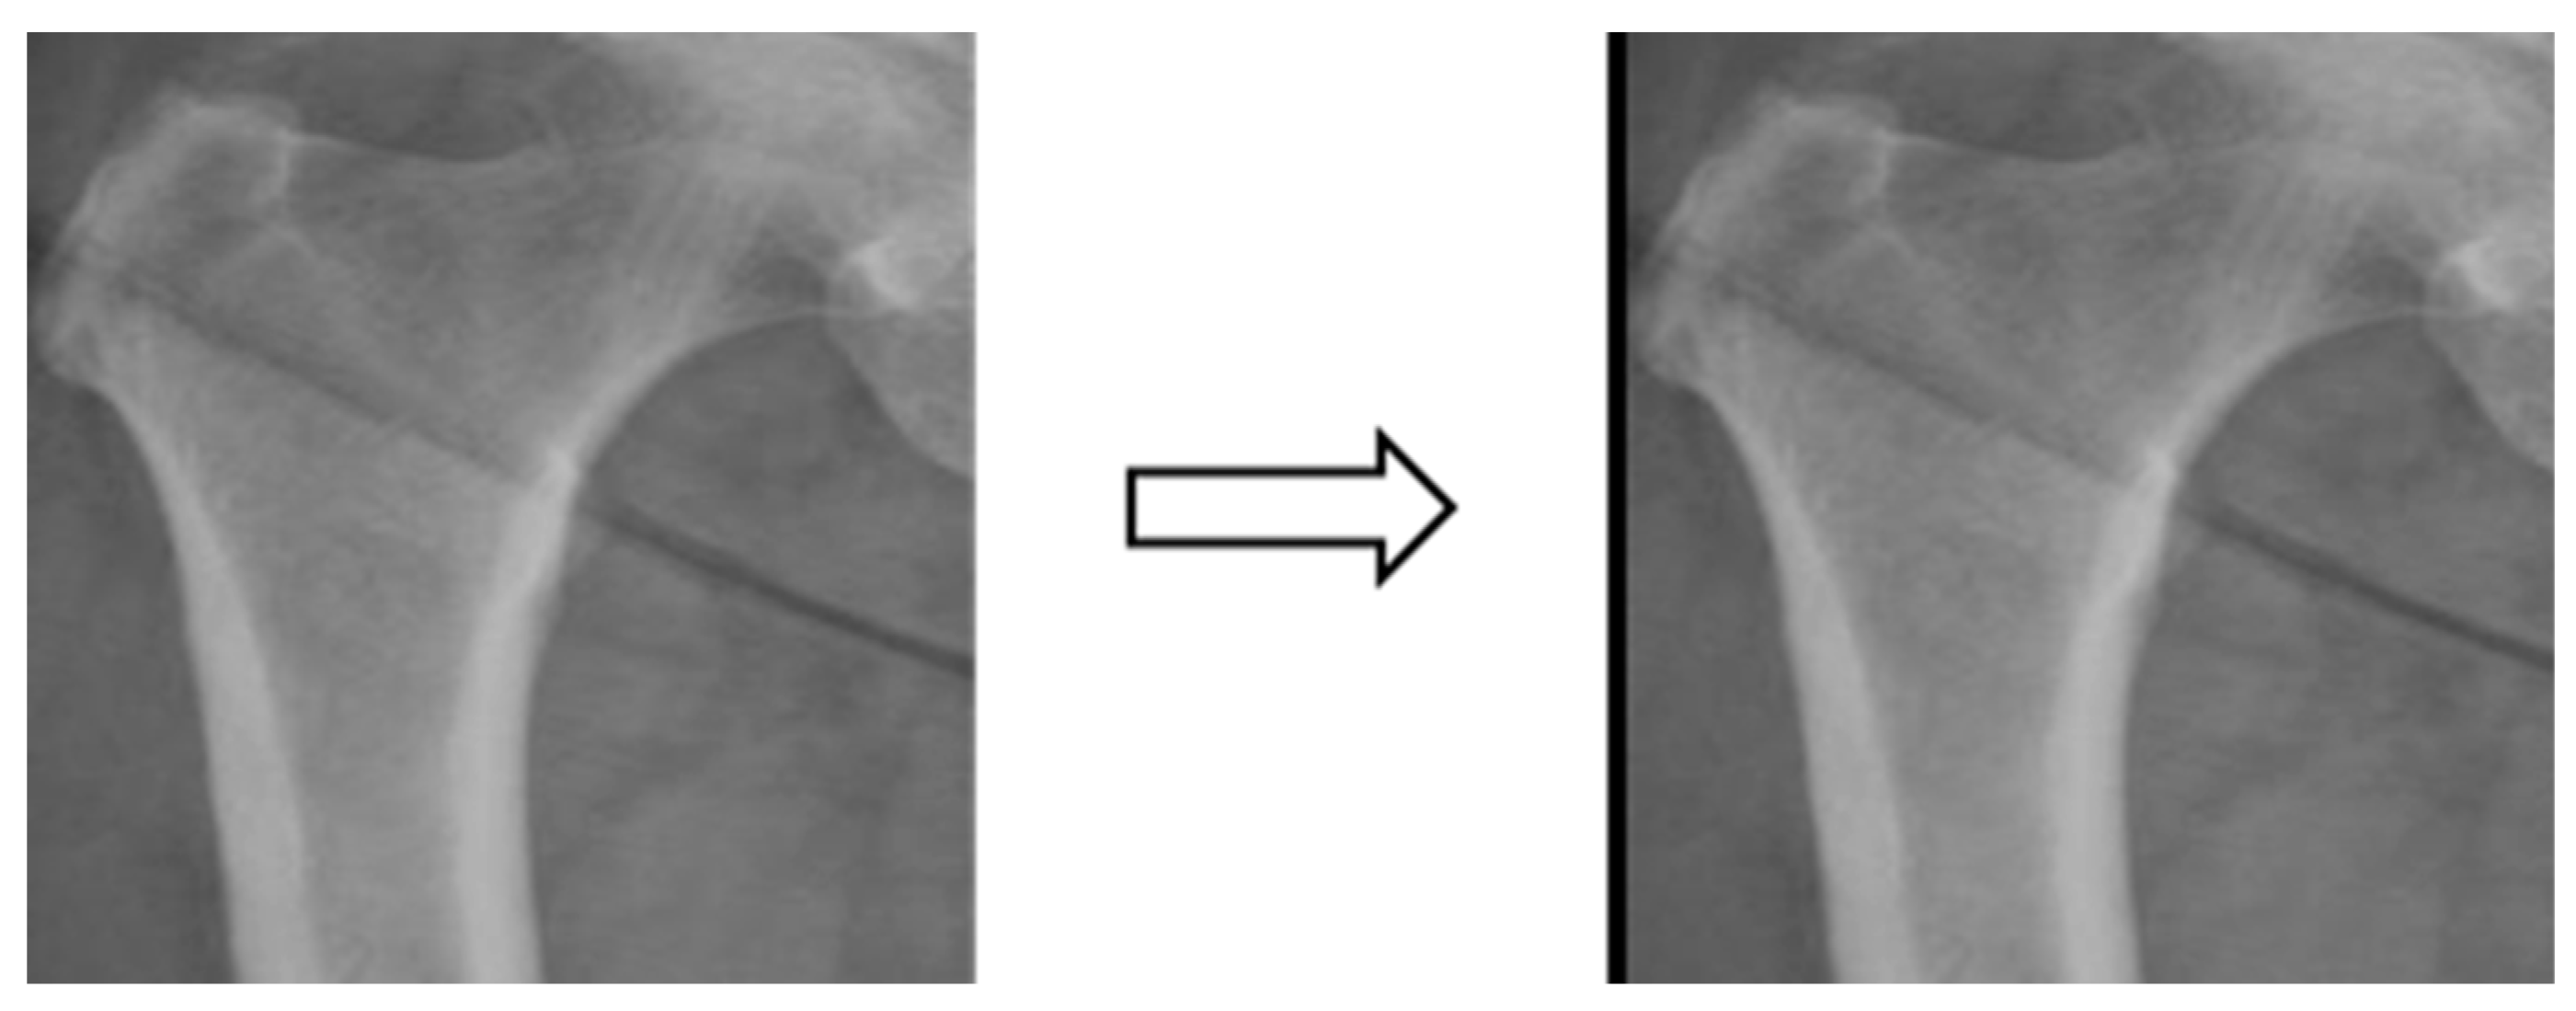

3.3.2. Image segmentation

In this study, four parts of the image labeled X-ray images were used in image segmentation by feeding them into U-Net and U-Net++ models for training, and the bit depth of the four parts of the image was converted from the original 24 bits to 8 bits before the model training. The reason for choosing to use U-Net and U-Net++ is that their model structure is simpler, it does not need to spend a lot of time to filter out the remaining noise in the medical images, and it is less likely to form overfitting for a small number of image datasets. The binary segmentation prediction results obtained after training the models of U-Net and U-Net++ are shown in Figure 3 below.